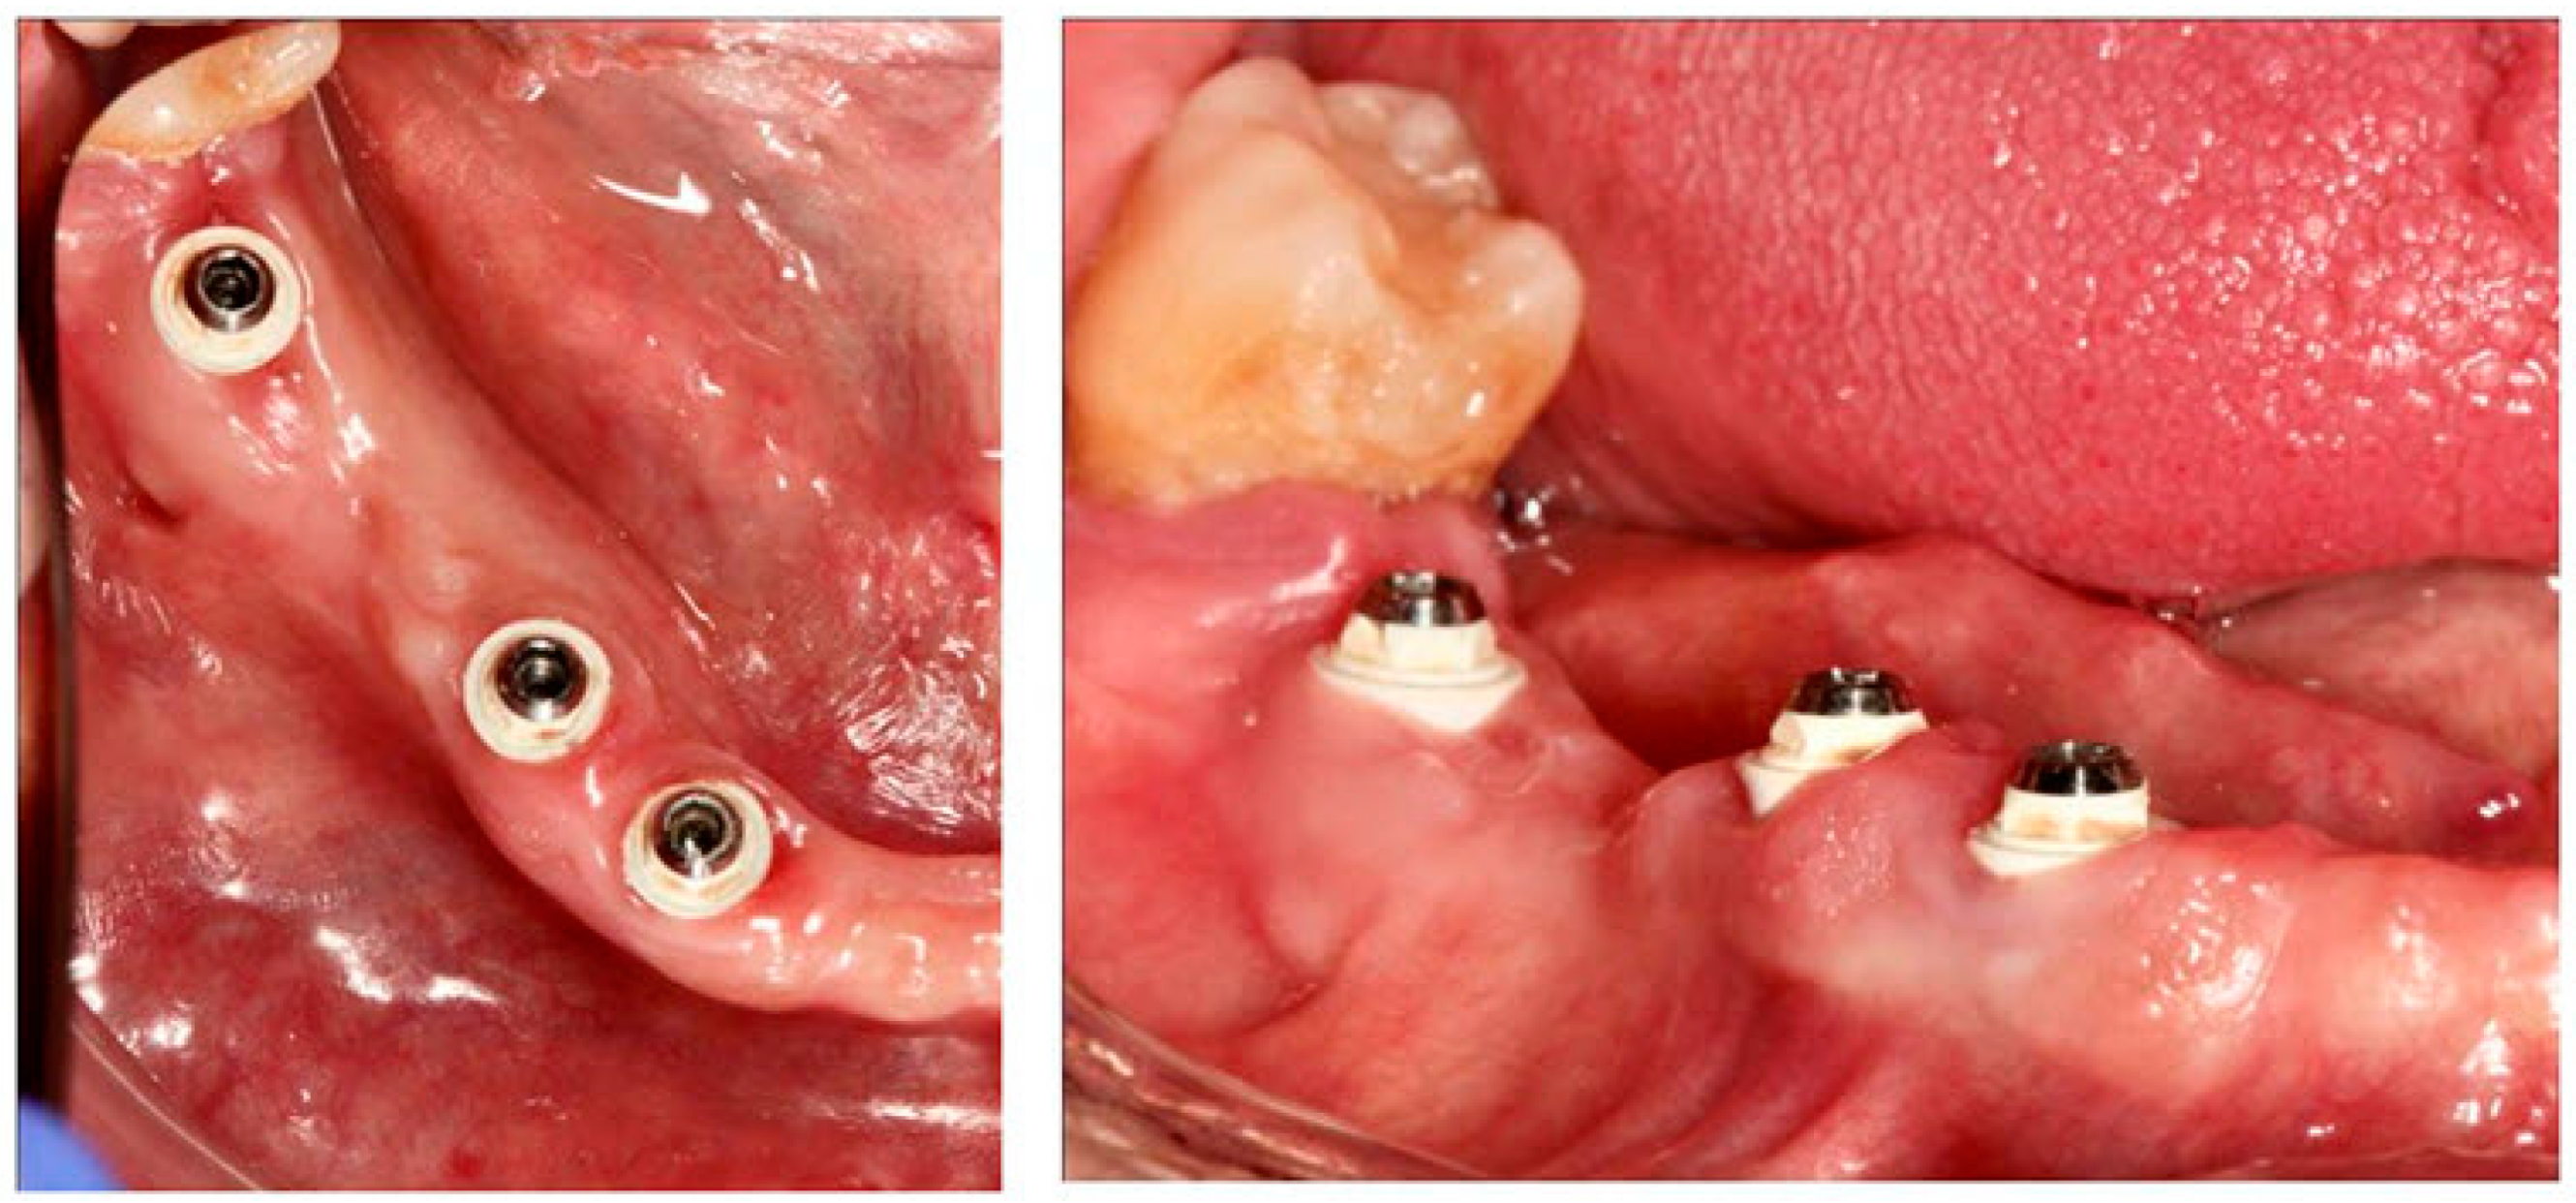

- The coating showed high biocompatibility and mechanical stability one year after implant insertion in a patient with periodontal problems.